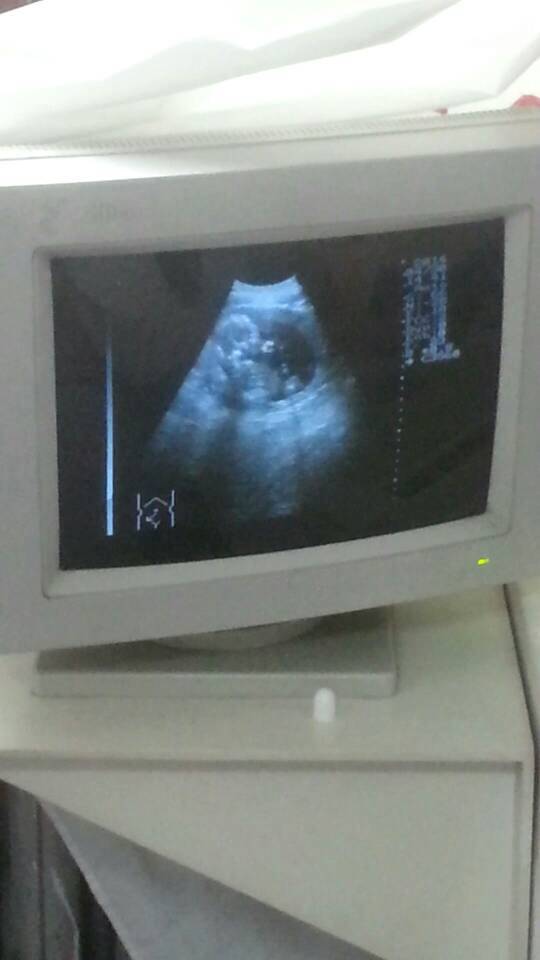

B超显示有三个小白点,有可能是小鸡鸡嘛?还是脐带呀

亲,小jj得几率大哦,估计是北鼻